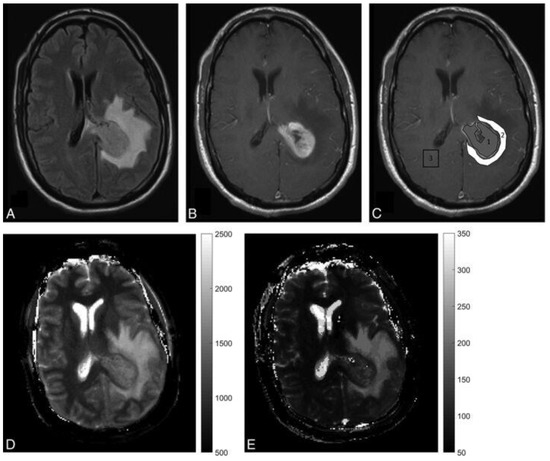

- Badve, C.; Yu, A.; Dastmalchian, S.; Rogers, M.; Ma, D.; Jiang, Y.; Margevicius, S.; Pahwa, S.; Lu, Z.; Schluchter, M.; et al. MR Fingerprinting of Adult Brain Tumors: Initial Experience. Am. J. Neuroradiol. 2017, 38, 492–499. [Google Scholar] [CrossRef] [PubMed]

- Dastmalchian, S.; Kilinc, O.; Onyewadume, L.; Tippareddy, C.; McGivney, D.; Ma, D.; Griswold, M.; Sunshine, J.; Gulani, V.; Barnholtz-Sloan, J.S.; et al. Radiomic analysis of magnetic resonance fingerprinting in adult brain tumors. Eur. J. Nucl. Med. Mol. Imaging 2021, 48, 683–693. [Google Scholar] [CrossRef] [PubMed]

- Haubold, J.; Demircioglu, A.; Gratz, M.; Glas, M.; Wrede, K.; Sure, U.; Antoch, G.; Keyvani, K.; Nittka, M.; Kannengiesser, S.; et al. Non-invasive tumor decoding and phenotyping of cerebral gliomas utilizing multiparametric 18F-FET PET-MRI and MR Fingerprinting. Eur. J. Nucl. Med. Mol. Imaging 2019, 47, 1435–1445. [Google Scholar] [CrossRef]